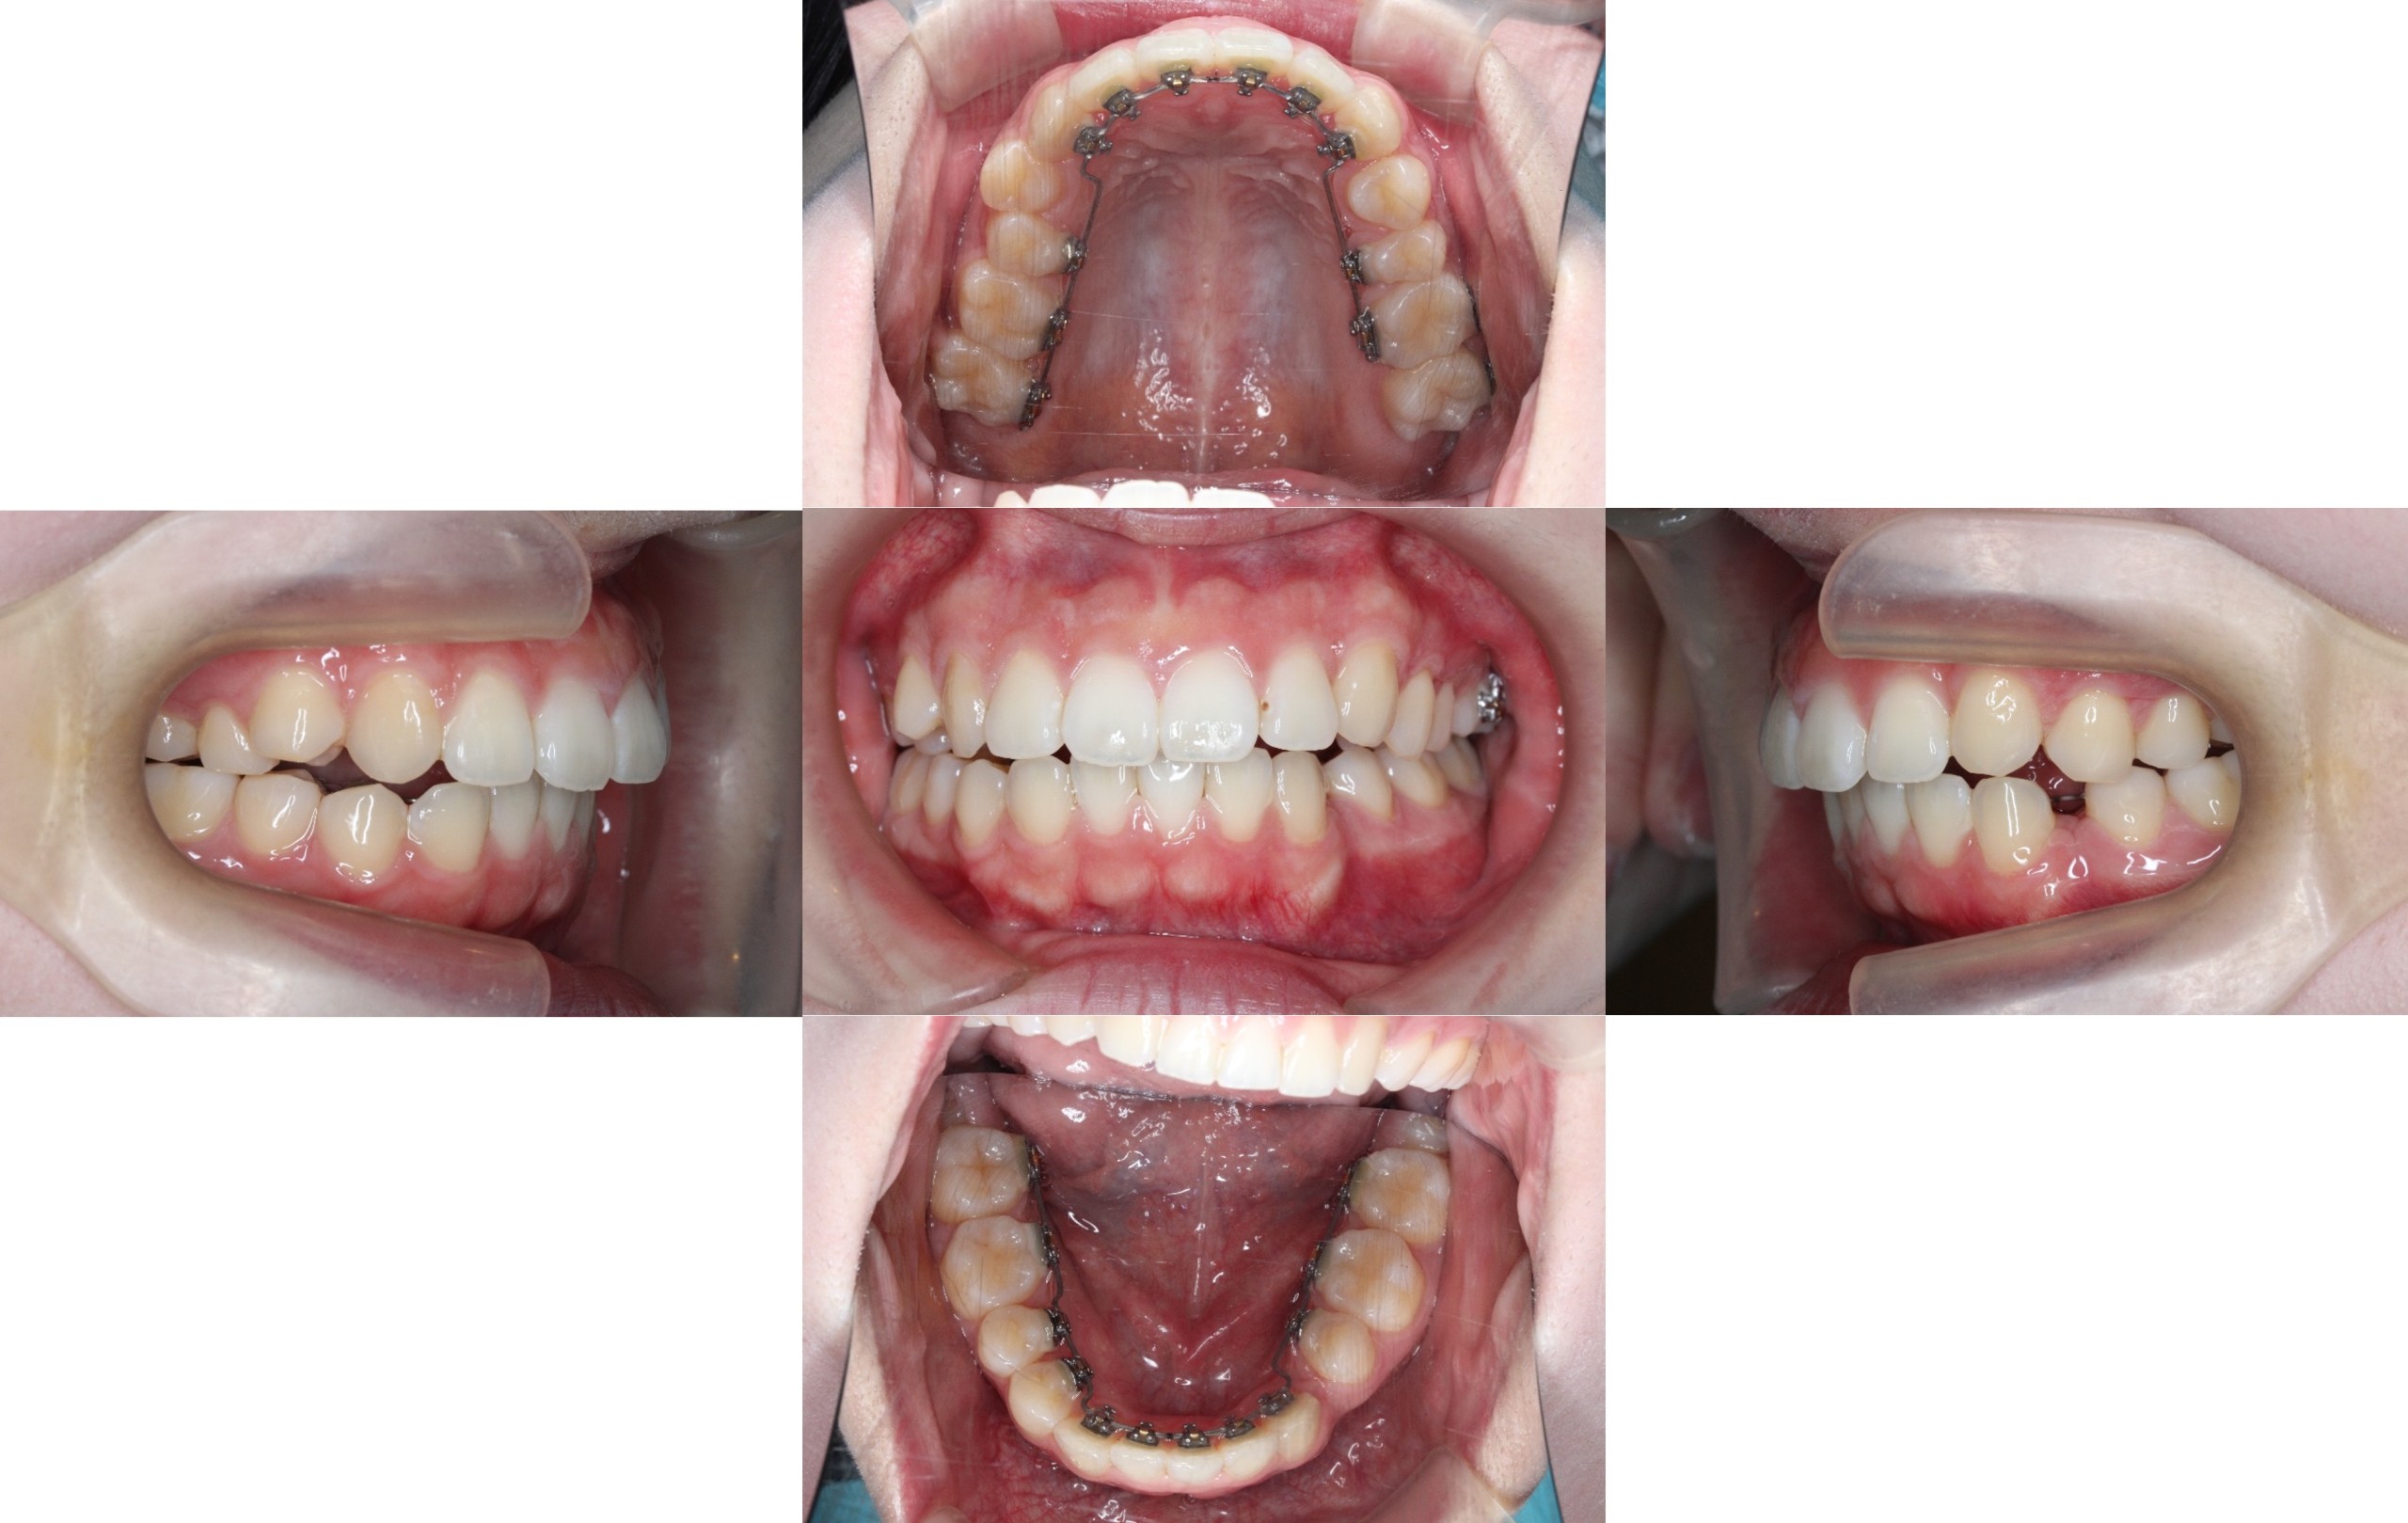

約半年経過

約1年経過